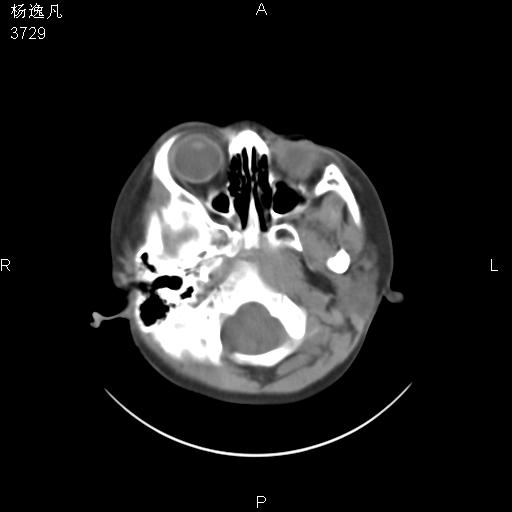

男性,5岁,面部受外伤,余无特殊

软组织窗

1、右面部及颞部软组织肿胀。

2、腺样体肥大。

头颅ct平扫未见明确外伤性征象,右侧面部及颞部软组织肿胀,后鼻腔软组织影增大,增厚,鼻咽顶部变窄,考虑鼻咽腺样体增值肥厚。